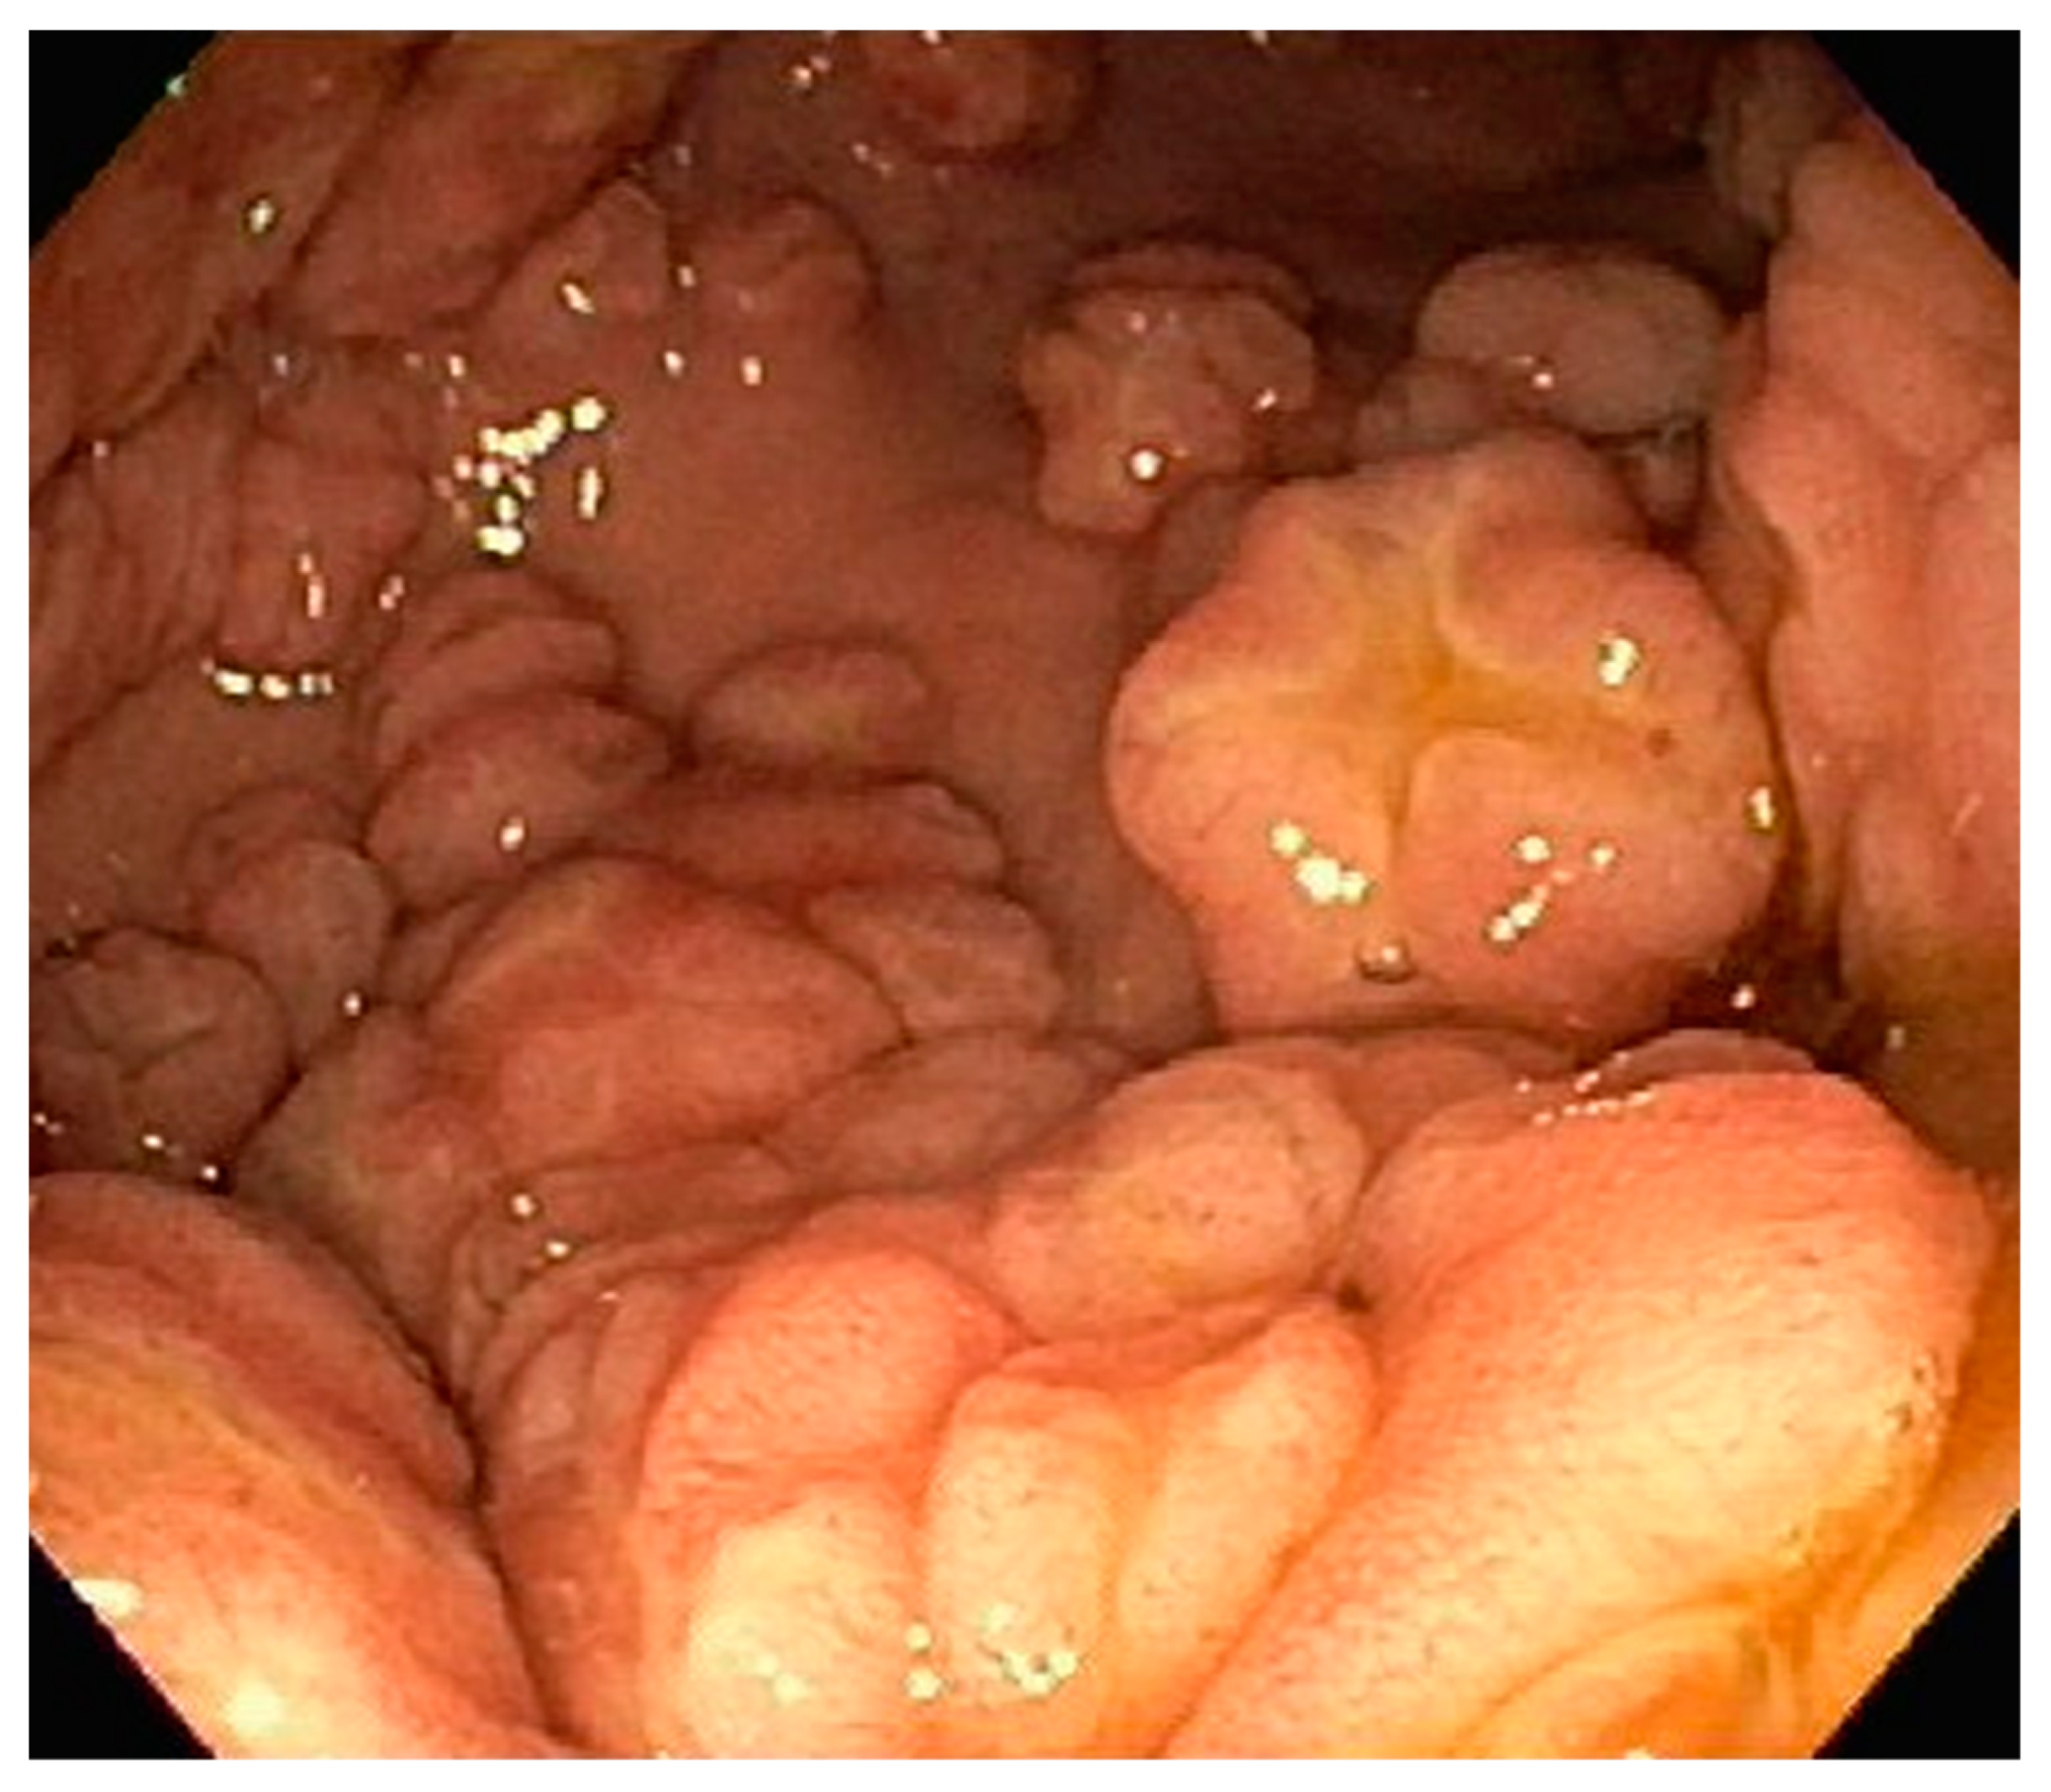

| 1 | F | 66 | Skin | Fundus, cardia, and body | Polypoid lesions with superficial ulcers | Esophagus, duodenum, mediastinum, cervical soft tissue, pancreas | Metastatic malignant melanoma | Radiotherapy and immunotherapy | Comfort care and death 5 days after EGD diagnosis of metastasis |

| 2 | M | 84 | Lymphoid | Fundus and cardia | Ulcerated and necrotic mass | Liver, urinary bladder | Diffuse large B-cell lymphoma | None | Death in 2 months after EGD diagnosis of metastasis |

| 3 | F | 35 | Lung | Fundus | Fungating mass | Esophagus, mediastinum | Large-cell neuroendocrine carcinoma | Chemotherapy-carboplatin/ etoposide | Death 1 month after EGD diagnosis of metastasis |

| 4 | F | 73 | Kidney | Fundus and body | Multiple large friable masses | Liver and lungs | Clear cell renal carcinoma | Nephrectomy, chemotherapy, immunotherapy (Axitinib) | Death 10 days after EGD diagnosis of metastasis |

| 5 | M | 76 | Lung | Body | Cratered ulcers | Liver, bone and adrenals | Small cell carcinoma (poorly differentiated neuroendocrine Ca) | None | Death 7 days after EGD diagnosis of metastasis |

| 6 | M | 61 | Lymphoid | Unknown | Clean based ulcer | None | Marginal zone lymphoma | Rituximab, Zanubrutinib, umbrasilib. OCHOP regimen currently | Progressive disease per latest scans despite therapy |